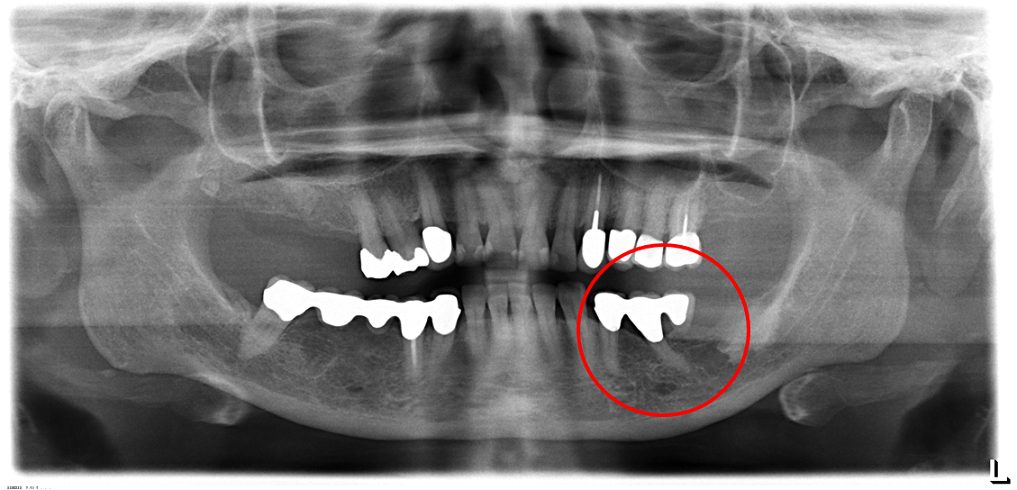

01/02 - Radiographic view before periodontal regenerative therapy with Straumann® Emdogain®. A deep intrabony defect appeared mesially and distally on the left mandibular first premolar. Pre-surgical probing measured 8 mm. The defect morphology presented as well-contained.

Contained intrabony defect treated using Straumann® Emdogain® - Prof. Dr. Dr. A. Kasaj